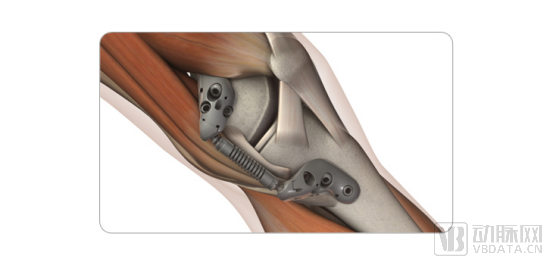

MISHA膝关节植入物由两个分别固定在股骨远端和胫骨近端的底座,以及在两个底座中间的吸收器,外加6支固定底座的螺钉组成。该产品按已完全组装状态供应,并有大小左右之分。其通过内侧囊外空间的皮下组织中的单个切口植入,使用锁定螺钉固定到股骨远端和胫骨近端的内侧皮质上。植入物与内侧膝关节一起分担负荷,关节球窝使得该装置可以适应膝关节的自然运动。

与全膝关节置换手术(TKA)不同,患者的骨骼、肌肉、韧带或软骨无需切除,也不会破坏关节囊,从而最大限度地加快了患者的恢复周期,并且康复后对患者没有活动限制,不会影响患者正常的运动、工作和生活。更为重要的是,该植入物只是放置在皮肤下而不会在结构上改变关节,这为患者未来的治疗方案保留了可选择性。

当植入者膝盖弯曲和抬起时,MISHA膝关节系统植入物就像汽车减震器一样,可以减少疼痛膝关节上的峰值力